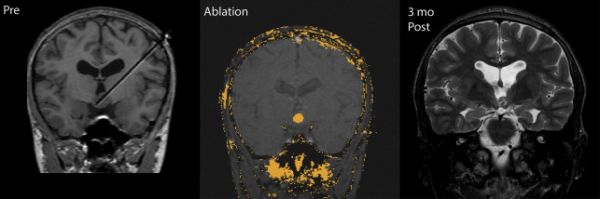

<LITT技术去除癫痫病灶前后效果>

<LITT技术消融脑内胶质瘤前后效果图>